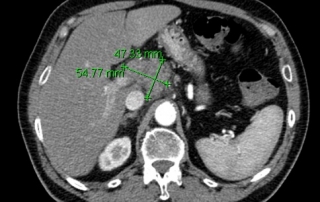

Gastroscopie et écho-endoscopie digestive : estomac normal. Adénopathies coeliaques confluentes, pancréas normal.

Biopsie d’une adénopathie sus-claviculaire conduit au diagnostic de lymphome diffus à grandes cellules B CD20+, CD5-, CD10-, BCL6+, BCL2 faible. Biopsie médullaire normale.

Classement LNH diffus à grandes cellules B CD20+, stade III, OMS = 1, LDH augmentées soit 2 facteurs selon IPIaa.

Décision : R-CHOP21 x 8 cycles avec prophylaxie neuro-méningée par 4 PL méthotrexate, en raison de l’IPIaa à 2 et des LDH augmentée. Evaluation par scanner après 4 cycles et par TEP-FDG après 8 cycles.

Classement rémission complète avec adénomégalies résiduelles sous- diaphragmatiques non hypermétaboliques